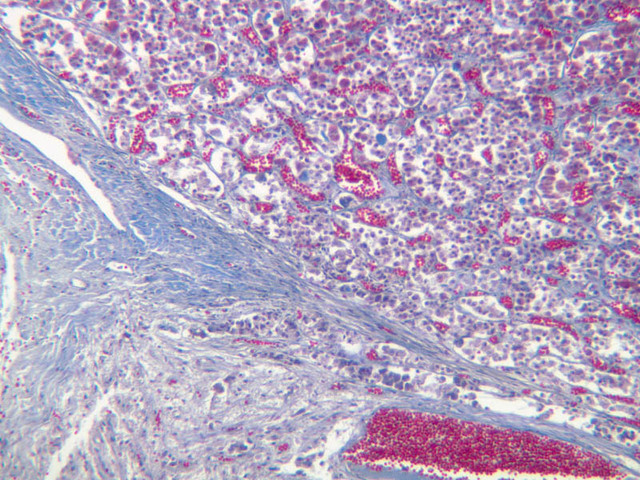

The adrenal gland (slide B-59, H&E [2.5x-labeled, 10x-labeled, 20x, 40x-labeled] [2.5x, 10x-labeled, 20x, 40x]; B-60, H&E [2.5x-labeled, 10x, 20x, 40x]; B-62, H&E [10x, 20x, 40x] [2.5x, 10x]) is a composite organ consisting of two functionally, structurally and embryologically different parts—an outer cortex and an inner medulla. Observe the gland at low power. Find the loosely organized tissue that comprises the medulla and the partially-separated columns of cells that make up the cortex. Scan the capsule and the tissue around it, looking for nerves and blood vessels. Study the pattern of cortical vasculature. In a pattern similar to that seen in the pars distalis of the pituitary, sinusoids run along the edges of columns or cords of cells. Owing to different arrangements of its constituent cells, the adrenal cortex has a layered appearance. From the capsule inward, these cortical layers are known as the zona glomerulosa, the zona fasciculata, and the zona reticularis.

The zona glomerulosa is located immediately beneath the capsule (B-60 adrenal gland, dog [10x, 20x] [20x, 40x]; B-59 [2.5x, 10x, 20x] [2.5x, 10x, 20x]). Its constituent cells are arranged in arcs or spheres, and, owing to their relatively small size, their nuclei appear to be close together. Cells of the zona glomerulosa secrete mineralocorticoids (e.g., aldosterone). The zona fasciculata consists of parallel columns or cords of cells that radiate toward the medulla and are separated by blood sinusoids (B-60 [2.5x, 10x, 20x, 40x]; B-62 [20x, 40x]). Owing to the extraction of lipids during histological processing, the cytoplasm of cells in the zona fasciculata appears highly vacuolated or "foamy". Cells of the zona fasciculata secrete glucocorticoids (e.g., hydrocortisone & cortisone) and some gonadocorticoids (weak androgens). The zona reticularis is the deepest cortical layer and lies adjacent to the medulla (B-60 [20x, 40x]; B-62 [20x, 40x]). It is characterized by irregular, interconnecting cords of cells which are separated by anastomosing capillary networks or sinusoids. Cells of the zona reticularis, which are smaller than those of zona fasciculata and do not contain as many lipid vacuoles, secrete gonadocorticoids and some glucocorticoids.

The medulla is composed of large epithelioid cells, arranged in small groups or cords which are separated by blood vessels. Usually, several large veins mark the center of the medulla. When fresh adrenal gland is incubated in solutions of chromium salts (as was the specimen on slide B-61), brownish precipitates form in the cells of the medulla-- hence, the name chromaffin cell (B-61, chromaffin [2.5x, 10x, 20x, 40x] [2.5x, 10x, 20x, 40x-labeled]). The more darkly stained chromaffin cells are known to contain norepinephrine, the less darkly stained cells, epinephrine. In essence, chromaffin cells are specialized postganglionic sympathetic neurons. How does the ultrastructure of these cells differ from that of the secretory cells of the adrenal cortex?